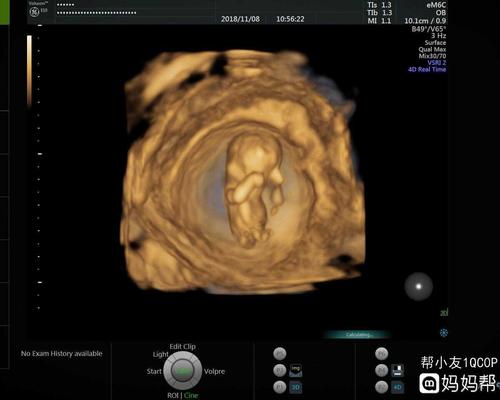

12周男孩女孩分化图,彩超三个月男胎儿图片

终于熬到12周 ,不知道男孩女孩,一定要健健康康的!

12周的nt 看着像男孩还是女孩

12周3天拍的b超,医生说看不清男孩女孩,好像是个女孩.

12周做nt心率180是不是有点快,宝妈们能看出男孩女孩吗?

彩超三个月男胎儿图片

孕12周胎儿小鸡彩超图

b超看男孩女孩图12周

12周胎儿图片真实图片

12周胎儿性别发育图

孕十二周男女胎儿图

孕12周男孩nt图片

怀孕12周彩超图片

孕12周男宝生殖彩超图

12周男宝b超图片

12周胎儿高清男孩图片

孕12周胎儿男女生殖